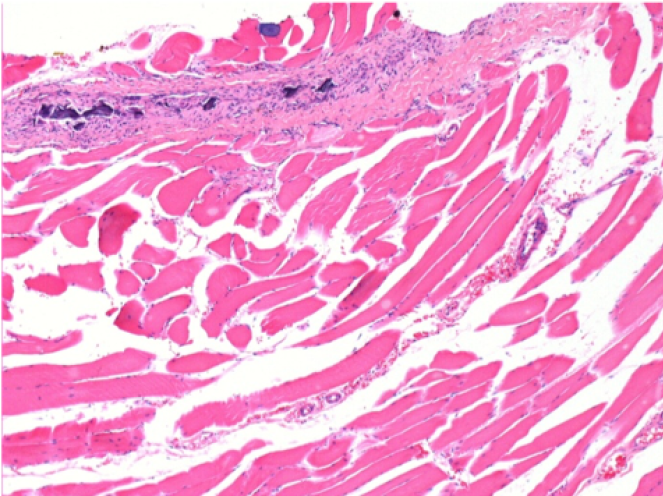

0.5 ml ( 5x 0.1ml) Endopeel SC Injection in the right subcutaneous pretibial area.

L:200x-Control-SC

R-D10-SC-200X